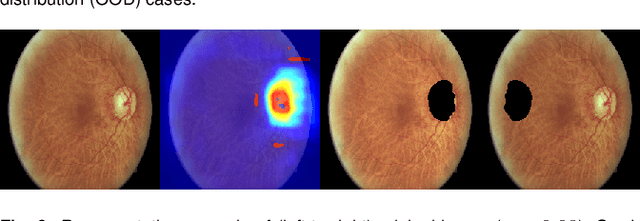

Abstract:Diabetic retinopathy (DR) grading is crucial in determining the patients' adequate treatment and follow up, but the screening process can be tiresome and prone to errors. Deep learning approaches have shown promising performance as computer-aided diagnosis(CAD) systems, but their black-box behaviour hinders the clinical application. We propose DR$\vert$GRADUATE, a novel deep learning-based DR grading CAD system that supports its decision by providing a medically interpretable explanation and an estimation of how uncertain that prediction is, allowing the ophthalmologist to measure how much that decision should be trusted. We designed DR$\vert$GRADUATE taking into account the ordinal nature of the DR grading problem. A novel Gaussian-sampling approach built upon a Multiple Instance Learning framework allow DR$\vert$GRADUATE to infer an image grade associated with an explanation map and a prediction uncertainty while being trained only with image-wise labels. DR$\vert$GRADUATE was trained on the Kaggle training set and evaluated across multiple datasets. In DR grading, a quadratic-weighted Cohen's kappa (QWK) between 0.71 and 0.84 was achieved in five different datasets. We show that high QWK values occur for images with low prediction uncertainty, thus indicating that this uncertainty is a valid measure of the predictions' quality. Further, bad quality images are generally associated with higher uncertainties, showing that images not suitable for diagnosis indeed lead to less trustworthy predictions. Additionally, tests on unfamiliar medical image data types suggest that DR$\vert$GRADUATE allows outlier detection. The attention maps generally highlight regions of interest for diagnosis. These results show the great potential of DR$\vert$GRADUATE as a second-opinion system in DR severity grading.